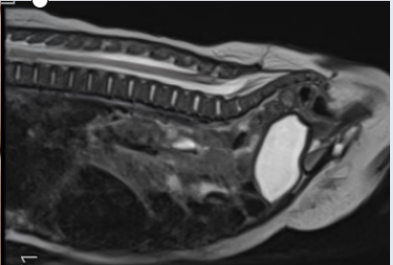

我在宝宝骶尾部的「躲藏」之路在 MR 面前原形毕露

看到这里,其实也不要过于担忧,悄悄告诉你,我也有害怕的时候。我害怕医院的影像学医生,因为他暴露了我的「秘密」通道(超声检查可以准确地显示并评估皮毛窦的形态、部位和走行方向、是否与椎管内相通、圆锥位置是否低、圆锥末端有无异常回声出现外,还可行 MRI 检查,尽可能发现合并的其他异常),更害怕外科医生,因为他一言不合就「开打」,毕竟我最大的威胁是手术。

如果产前超声检查能准确地显示并评估皮毛窦的形态、部位和走行方向、是否与椎管内相通、圆锥位置是否低、圆锥末端有无异常回声,能为宝宝出生后的治疗和随访观察提供坚实有利的依据。